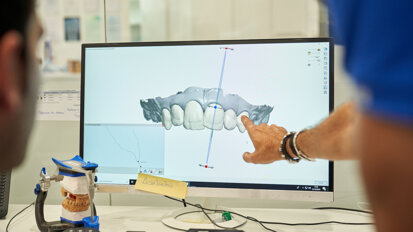

Rejestracja i przeniesienie zwarcia przebiegało w sposób zgodny z obowiązującymi standardami. Wykorzystano artykulator Stratos 200 z łukiem twarzowym (Ivoclar-Vivadent). Gotowe prace poddano symulacji okluzji w artykulatorze. U pacjentów GL i AA (przypadki: 1 i 2) wykonano korony Procera na łączniku indywidualnym z tlenku cyrkonu. W pozostałych przypadkach metalową część koron protetycznych wykonano z tytanu metodą odlewniczą lub techniką CAD/CAM. Olicowanie wykonano z porcelany TITANKERAMIK (VITA).